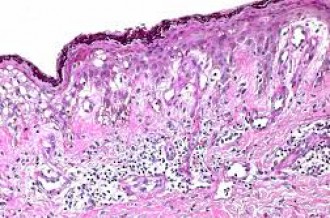

Il prelevamento mirato di una parte di cute (pelle) consente di studiare la natura della lesione e stabilire se si tratta di patologia malformativa (angioma, ecc.), infiammatoria (lichen, ecc.), autoimmune (psoriasi, ecc.), allergica (rush, ecc.), infettiva (pomfo, pemfigo, vescicola, ecc.), pre-neoplastica (lesione attinica, ecc.), neoplastica dell’epidermide (basalioma, ecc.) o di pertinenza melanocitaria (melanoma, ecc.), oltre che di una eventuale natura metastatica.

Le biopsie incisionali ripetute consentono di stabilire l’efficacia di una terapia pregressa e/o in atto.